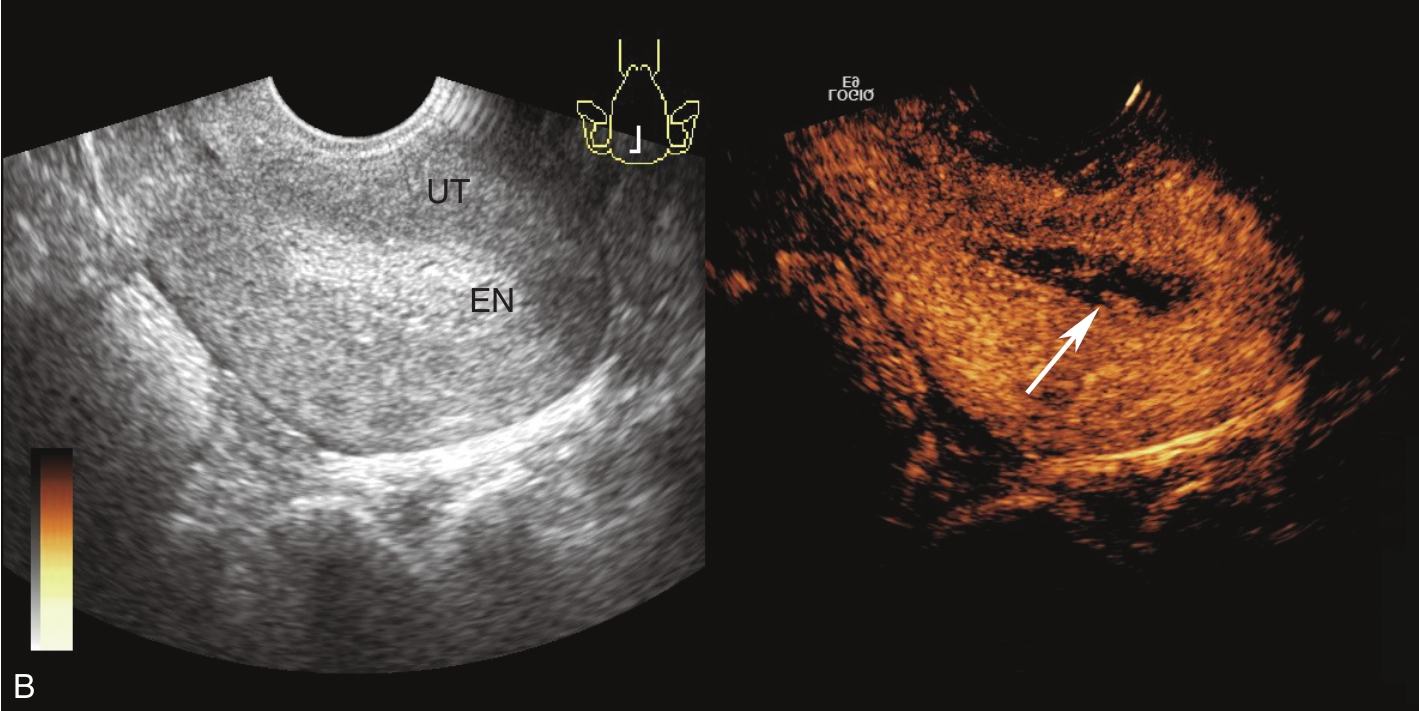

经阴道超声检查见图3-5-1。子宫后位,宫体大小约5.8cm×5.0cm×5.1cm,宫内膜厚约0.75cm(单层),内膜回声不均匀。宫腔未见分离。宫壁回声均匀。内膜内见多个囊性结节,较大者大小约0.5cm,内透声可。CDFI:未见异常血流信号。双侧附件区未见异常回声。盆腹腔未见明显积液。超声检查结果:宫内膜增厚伴回声不均匀。

图3-5-1 常规超声声像图

A.后位子宫的矢状切面(经阴道),子宫内膜增厚,单层厚约0.75cm,内见多个小暗区;B.后位子宫的横断面(经阴道);C.后位子宫的矢状切面(经阴道),彩色多普勒能量图超声检查显示子宫未探及明显血流信号;D.右卵巢;E.左卵巢。UT:子宫;EN:子宫内膜;R-OV:右卵巢;L-OV:左卵巢。